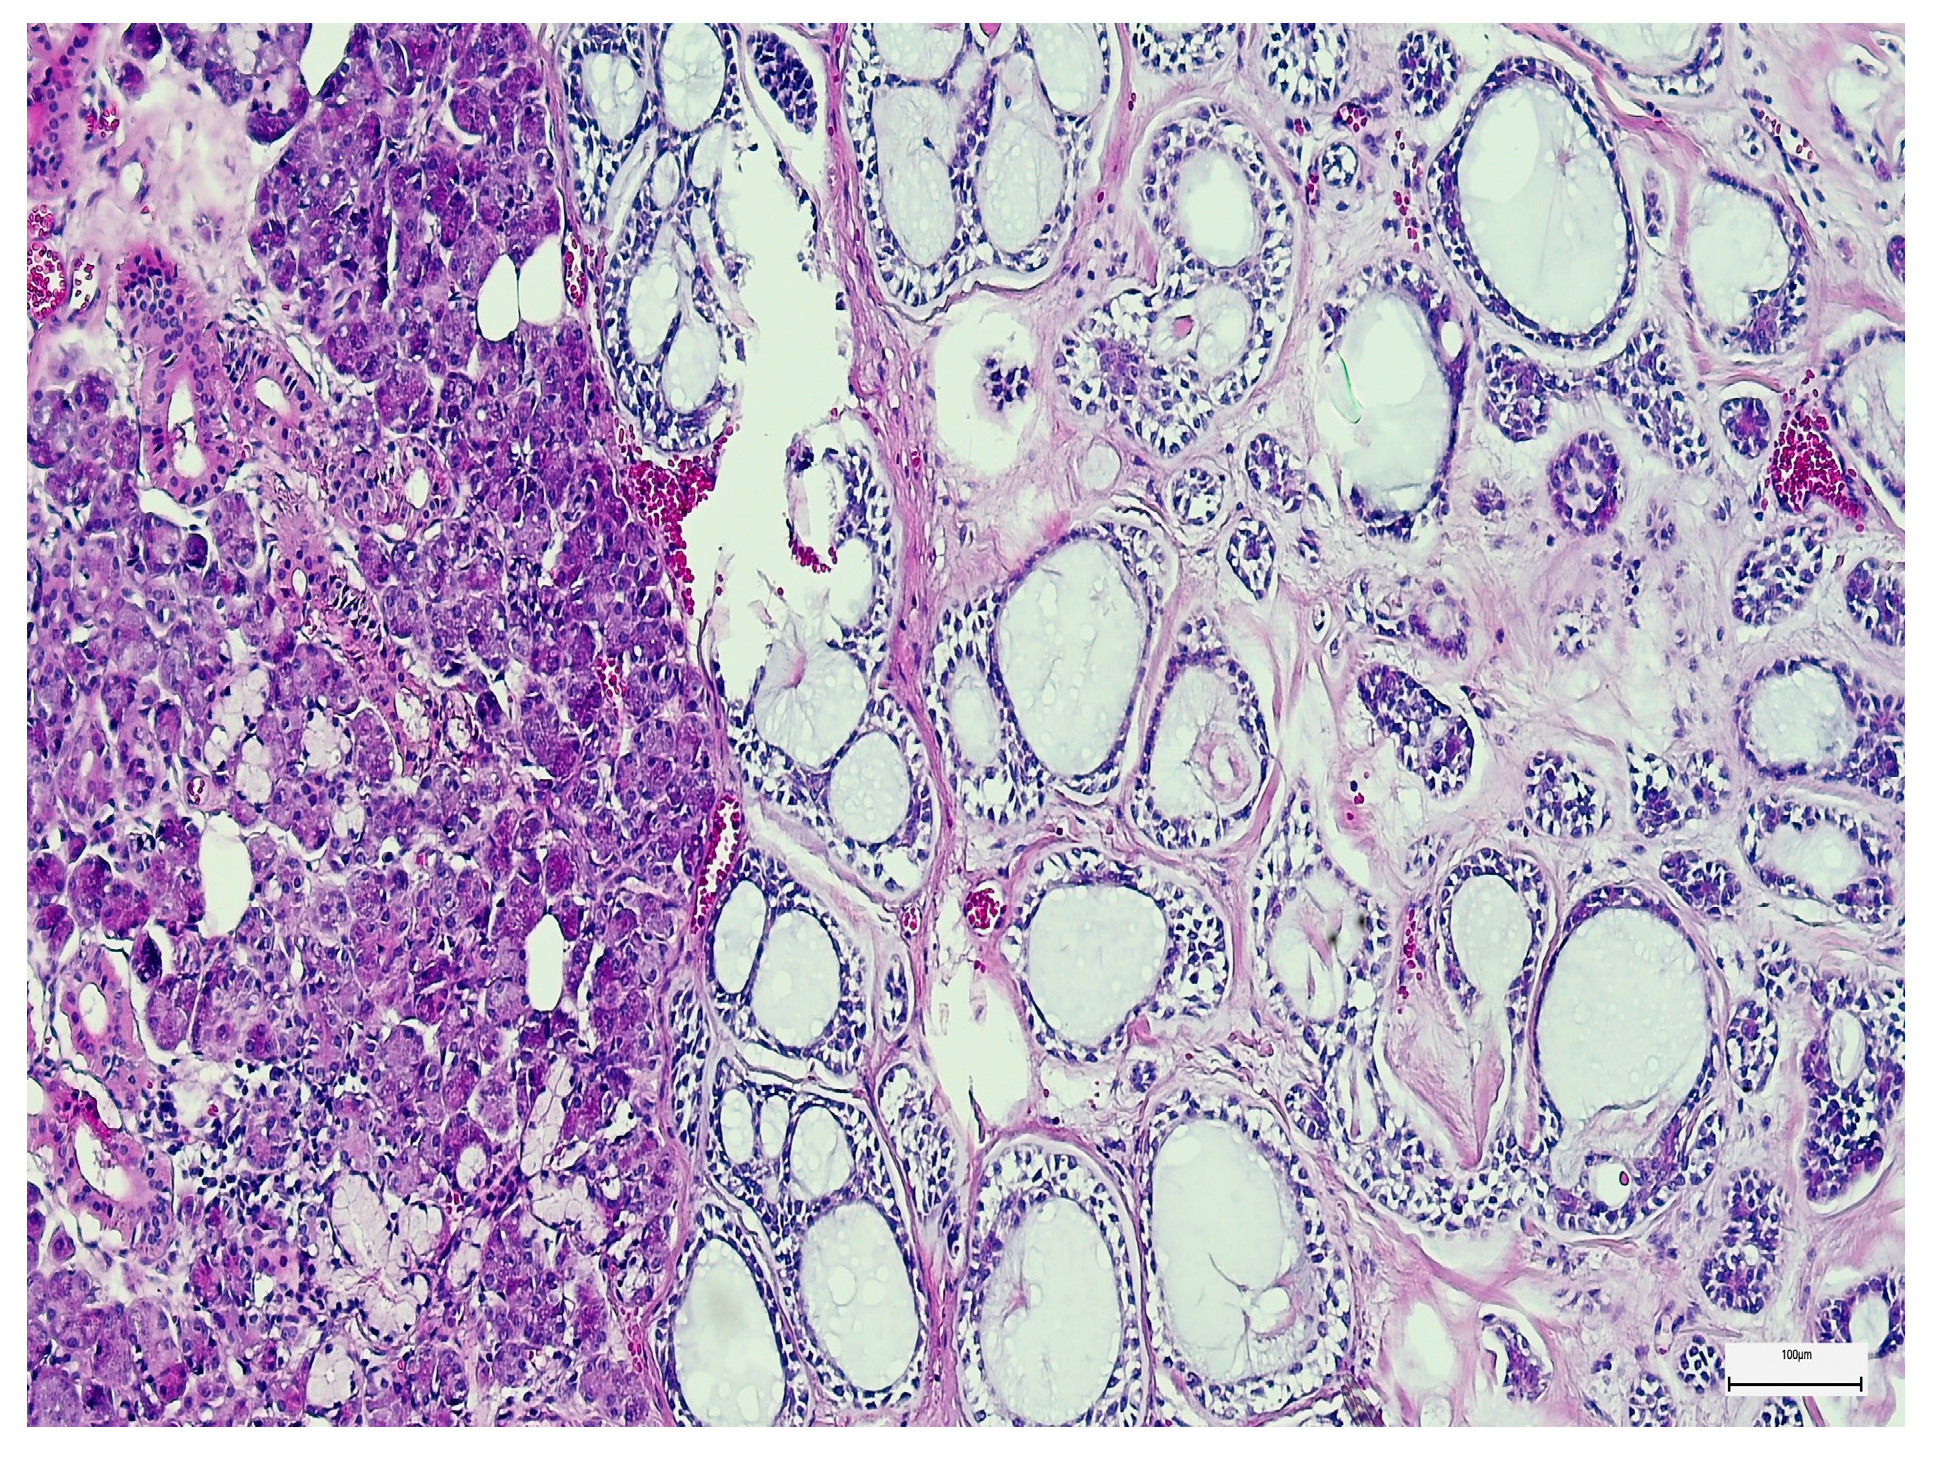

3. Results

3.2. Qualitative and Semi-Quantitative Assessment of SOX-2 and EZH-2 Immunoexpression